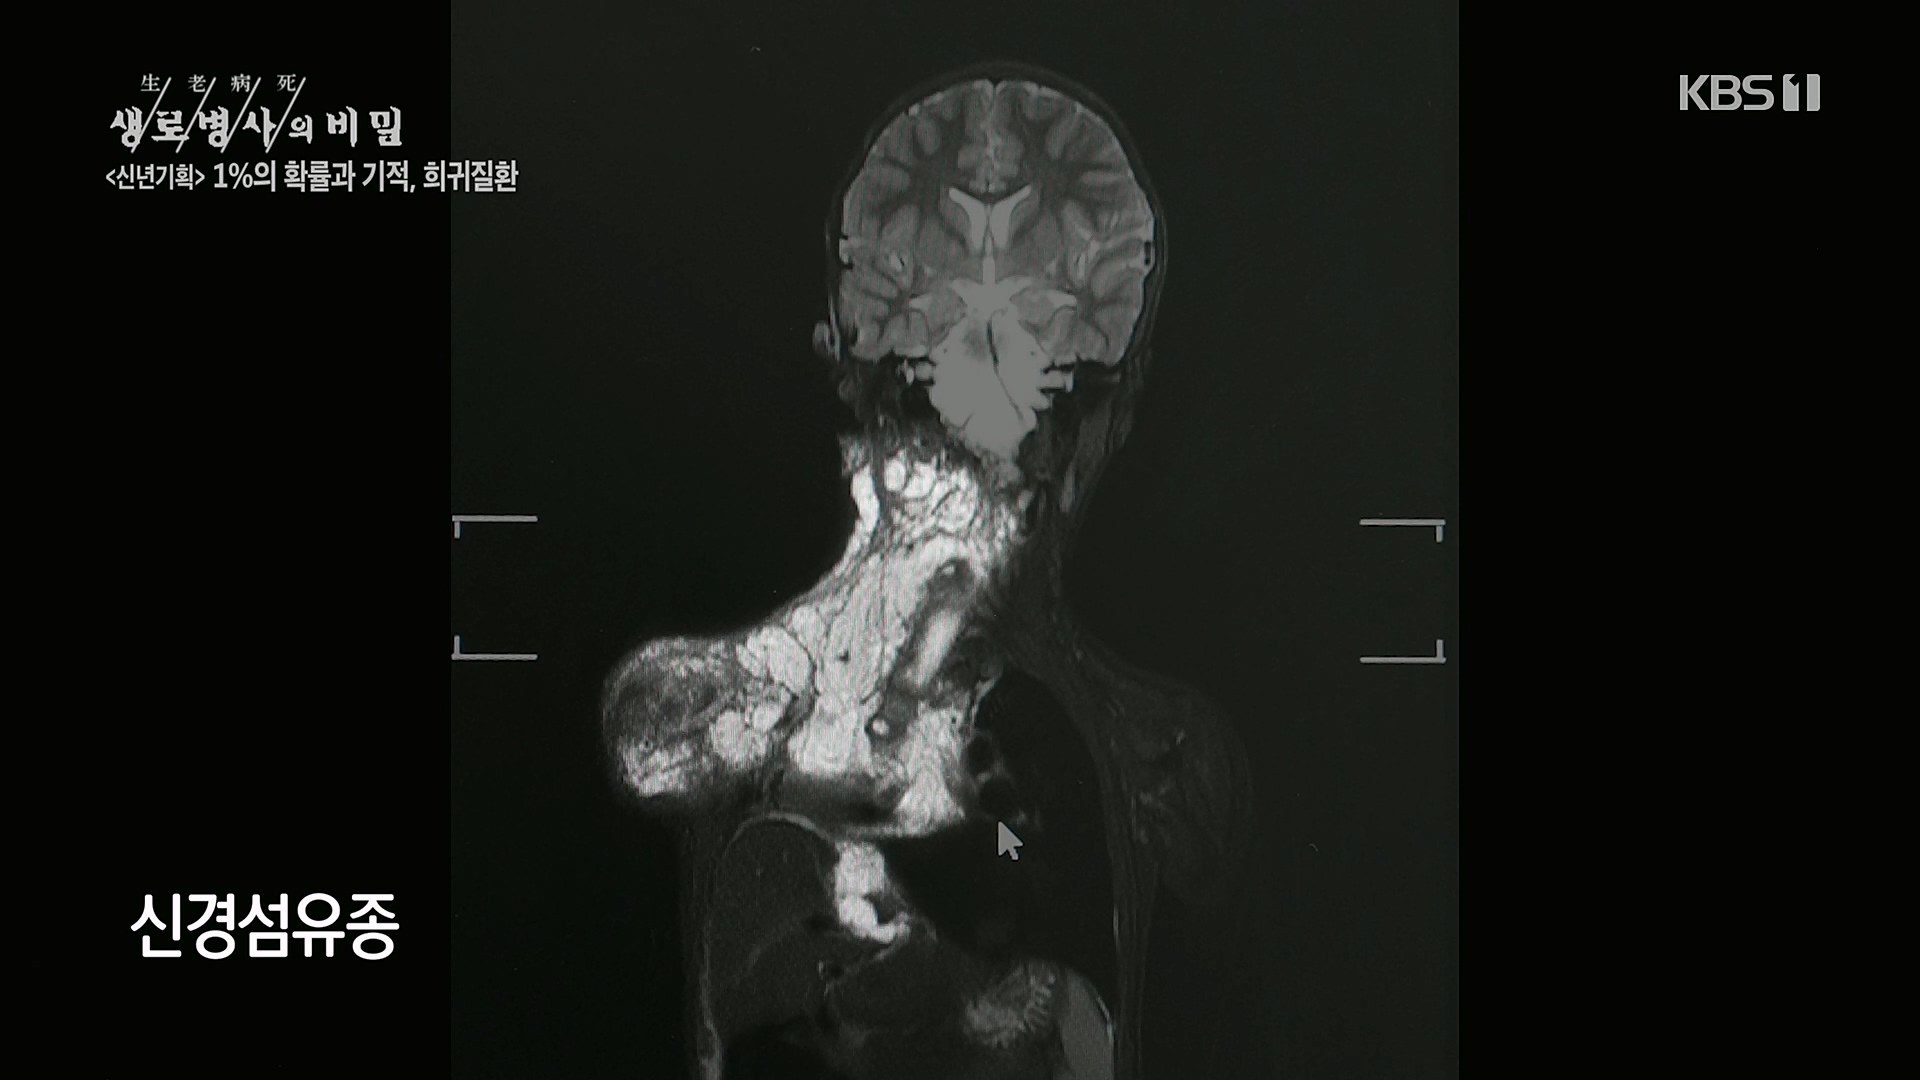

생로병사의 비밀.E850.230104p.H264-F1RST.mp4_20230117_194055.017.jpg 생로병사의 비밀.E850.230104p.H264-F1RST.mp4_20230117_194102.918.jpg 생로병사의 비밀.E850.230104p.H264-F1RST.mp4_20230117_195154.976.jpg 생로병사의 비밀.E850.230104p.H264-F1RST.mp4_20230117_195155.383.jpg 생로병사의 비밀.E850.230104p.H264-F1RST.mp4_20230117_195155.788.jpg 생로병사의 비밀.E850.230104p.H264-F1RST.mp4_20230117_195156.196.jpg 생로병사의 비밀.E850.230104p.H264-F1RST.mp4_20230117_195156.603.jpg 생로병사의 비밀.E850.230104p.H264-F1RST.mp4_20230117_195157.009.jpg 생로병사의 비밀.E850.230104p.H264-F1RST.mp4_20230117_195157.415.jpg 생로병사의 비밀.E850.230104p.H264-F1RST.mp4_20230117_195157.821.jpg 생로병사의 비밀.E850.230104p.H264-F1RST.mp4_20230117_195158.226.jpg 생로병사의 비밀.E850.230104p.H264-F1RST.mp4_20230117_195158.653.jpg 생로병사의 비밀.E850.230104p.H264-F1RST.mp4_20230117_195159.062.jpg 생로병사의 비밀.E850.230104p.H264-F1RST.mp4_20230117_195159.462.jpg 생로병사의 비밀.E850.230104p.H264-F1RST.mp4_20230117_195159.872.jpg 생로병사의 비밀.E850.230104p.H264-F1RST.mp4_20230117_195200.278.jpg 생로병사의 비밀.E850.230104p.H264-F1RST.mp4_20230117_195200.685.jpg 생로병사의 비밀.E850.230104p.H264-F1RST.mp4_20230117_195201.103.jpg 생로병사의 비밀.E850.230104p.H264-F1RST.mp4_20230117_195201.508.jpg 생로병사의 비밀.E850.230104p.H264-F1RST.mp4_20230117_195201.914.jpg 생로병사의 비밀.E850.230104p.H264-F1RST.mp4_20230117_195202.322.jpg 생로병사의 비밀.E850.230104p.H264-F1RST.mp4_20230117_195202.726.jpg 생로병사의 비밀.E850.230104p.H264-F1RST.mp4_20230117_195203.132.jpg 생로병사의 비밀.E850.230104p.H264-F1RST.mp4_20230117_195203.541.jpg 생로병사의 비밀.E850.230104p.H264-F1RST.mp4_20230117_195203.966.jpg 생로병사의 비밀.E850.230104p.H264-F1RST.mp4_20230117_195204.383.jpg 생로병사의 비밀.E850.230104p.H264-F1RST.mp4_20230117_195204.808.jpg 생로병사의 비밀.E850.230104p.H264-F1RST.mp4_20230117_195205.216.jpg 생로병사의 비밀.E850.230104p.H264-F1RST.mp4_20230117_195205.622.jpg 생로병사의 비밀.E850.230104p.H264-F1RST.mp4_20230117_195206.023.jpg 생로병사의 비밀.E850.230104p.H264-F1RST.mp4_20230117_195206.445.jpg 생로병사의 비밀.E850.230104p.H264-F1RST.mp4_20230117_195206.853.jpg 생로병사의 비밀.E850.230104p.H264-F1RST.mp4_20230117_195207.257.jpg 생로병사의 비밀.E850.230104p.H264-F1RST.mp4_20230117_195207.665.jpg 생로병사의 비밀.E850.230104p.H264-F1RST.mp4_20230117_195208.070.jpg 생로병사의 비밀.E850.230104p.H264-F1RST.mp4_20230117_195208.476.jpg 생로병사의 비밀.E850.230104p.H264-F1RST.mp4_20230117_195208.882.jpg 생로병사의 비밀.E850.230104p.H264-F1RST.mp4_20230117_195209.288.jpg 생로병사의 비밀.E850.230104p.H264-F1RST.mp4_20230117_195209.695.jpg 생로병사의 비밀.E850.230104p.H264-F1RST.mp4_20230117_195210.103.jpg 생로병사의 비밀.E850.230104p.H264-F1RST.mp4_20230117_195210.508.jpg 생로병사의 비밀.E850.230104p.H264-F1RST.mp4_20230117_195210.916.jpg 생로병사의 비밀.E850.230104p.H264-F1RST.mp4_20230117_195211.321.jpg 생로병사의 비밀.E850.230104p.H264-F1RST.mp4_20230117_195211.748.jpg 생로병사의 비밀.E850.230104p.H264-F1RST.mp4_20230117_195212.151.jpg 생로병사의 비밀.E850.230104p.H264-F1RST.mp4_20230117_195212.557.jpg 생로병사의 비밀.E850.230104p.H264-F1RST.mp4_20230117_195212.966.jpg 생로병사의 비밀.E850.230104p.H264-F1RST.mp4_20230117_195213.383.jpg 생로병사의 비밀.E850.230104p.H264-F1RST.mp4_20230117_195213.790.jpg